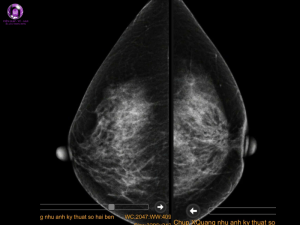

NHŨ ẢNH:

- Dày da vùng núm vú hai bên do núm vú bị tụt gây chồng ảnh.

- Vú trái vị trí 6g sát núm vú có khối đậm độ cao, bờ không đều, giới hạn rõ không kèm vi vôi.

- Kết luận: Tổn thương vú trái BI-RADS 4